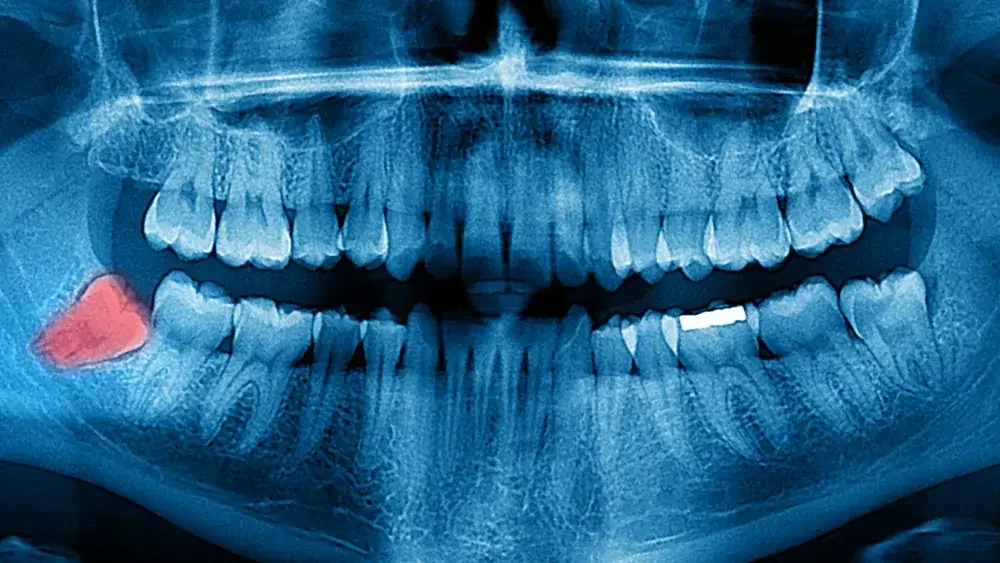

3. Rontgen Panoramik

Rontgen panoramik memberikan gambaran menyeluruh seluruh gigi, rahang atas dan bawah, sendi rahang, hingga sebagian area sinus. Pemeriksaan ini sering direkomendasikan untuk evaluasi gigi bungsu, perencanaan perawatan ortodonti (behel), pencabutan gigi kompleks, atau pemeriksaan awal sebelum tindakan lanjutan.